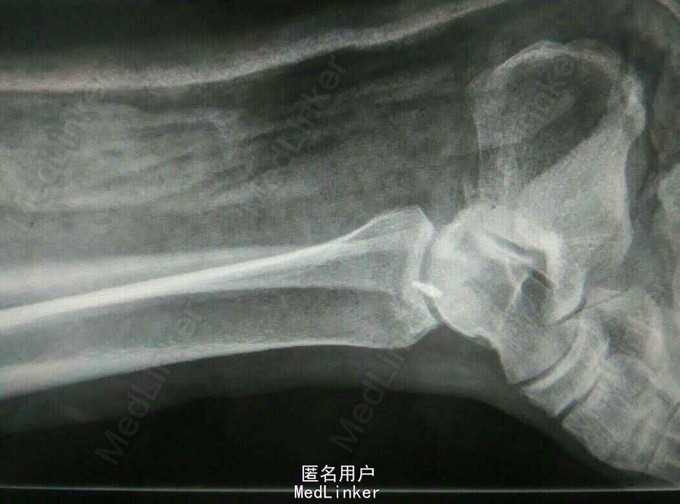

外伤致右踝关节疼痛肿胀,活动受限5小时 患者中年女性,因受外伤出现右踝关节疼痛、肿胀麻木,当即出现活动受限,急诊摄片提示内踝撕脱型骨折。

查体:右踝关节皮肤青紫,肿胀明显,内踝叩痛压痛明显,右足末梢感觉血运正常。 辅查:X线片提示右内踝撕脱性骨折。CT提示胫骨内踝骨折。

诊断:内踝骨折 治疗:右踝骨折切开复位内固定+三角韧带修复术